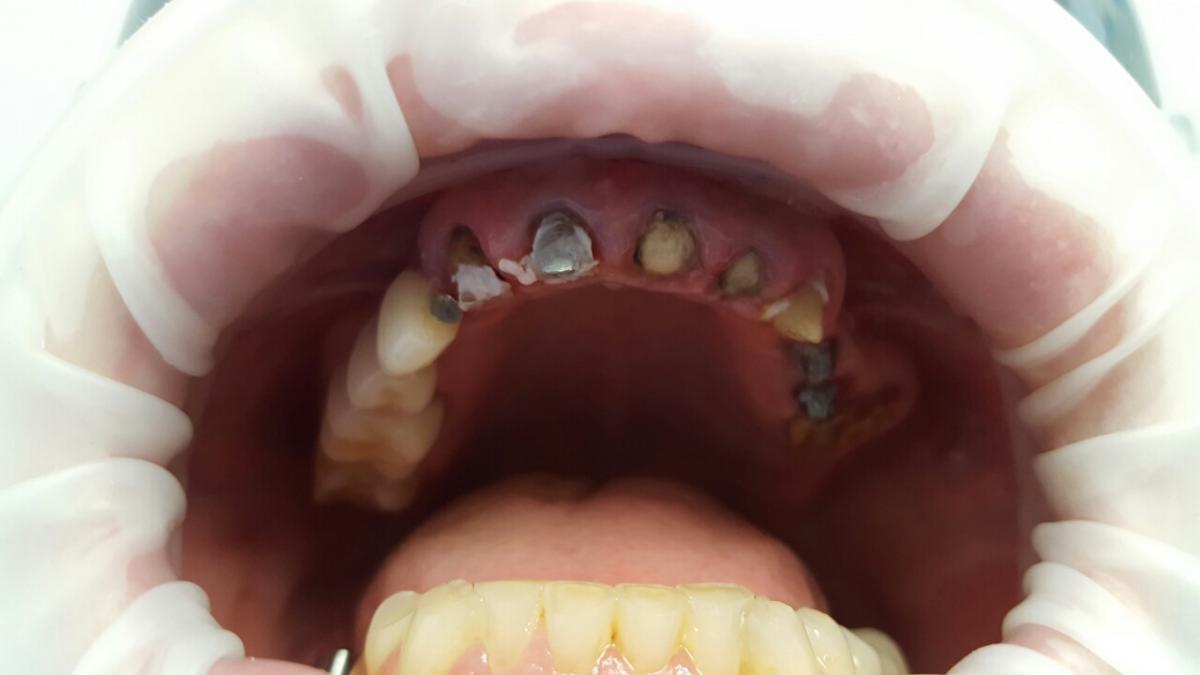

A patient case to the dental clinic with complaint connected with frond teeth defects. After the examination, he decided to provide dental treatment that includes immediate implantation of Alpha Dent implants. During the surgery he has placed 3 Alpha Dent implants in extracted teeth alveolar sockets. Then he placed allomaterial for bone regeneration over implants and sutured the wound.